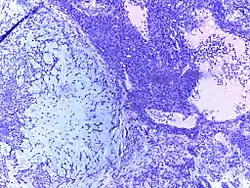

![]() |

Follicular lymphoma | Micrograph showing a small B-cell lymphoma compatible with follicular lymphoma. H&E stain. | Category: Histopathology of follicular lymphoma | Follicular lymphoma |